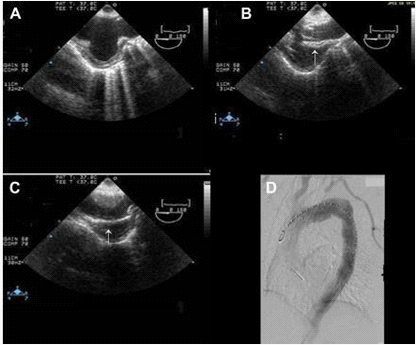

Figure 5 Image showing (A) arch aneurysm, (B) partially deployed stent graft (arrow), and (C) fully deployed stent graft (arrow). (D) Post procedure angiography showing stent grafts in place.28

In contrast, Echo Doppler has been recognized as a good option to these techniques due to its low cost, easy implementation and interpretation and the absence of exposure to any type of radiation.26 This provides a better understanding of the endoleak formation mechanism and provides a more accurate analysis thereof, due to a collateral circulation. The origins of an endoleak may also be correctly identified. Compounded by the fact that it allows visualize blood flow in the aneurysm sac and its direction. This seems to be an excellent tool in the evaluation of high flow endoleaks within the aneurysmal sac. It is an imaging technique commonly used in vascular studies, being easy to perform, inexpensive, portable, secure and highly available. Its use for patients’ follow-up can reduce the biological hazards associated with CT angiography, since this frees the body of the individual to a substantial dose of ionizing radiation. The advantage of Doppler ultrasound in patients’ follow-up with aortic stent graft is that it allows a serial measurement over time of the residual diameter of the aorticaneurysm sac. Doppler ultrasound is more accurate than CT for the detection of problems associated with stent graft patency, their migration, kinking and stenosis. Provides physiological and anatomical information at the same time, unlike CT. The ability to quantify and compare serial images at a low cost without contrast and radiation, suggests that this technique should be the Gold Standard in the follow-up to TEVAR (Figures 5-9).20,24,27